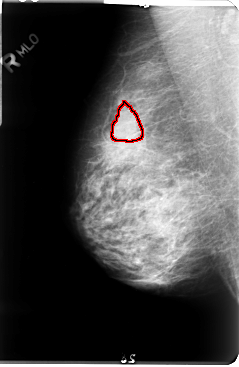

B_3048_1.RIGHT_CC

FILE: B_3048_1.RIGHT_CC.OVERLAY

TOTAL_ABNORMALITIES 1

ABNORMALITY 1

LESION_TYPE MASS SHAPE LOBULATED MARGINS CIRCUMSCRIBED-OBSCURED

ASSESSMENT 3

SUBTLETY 3

PATHOLOGY UNPROVEN

TOTAL_OUTLINES 1

BOUNDARY